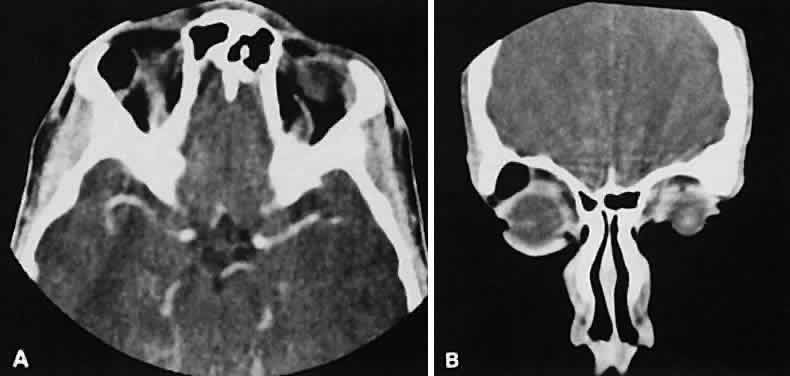

The edema and inflammatory infiltrate that accompany infections are indistinguishable from that associated with orbital inflammations. The presence of sinus disease, however, is a more constant feature with infections, because the sinus represents the infectious nidus in most cases (Fig. 9). In addition to the frequent appearance of sinus disease, the adjacent EOM is invariably enlarged. Less often, orbital infections may be transmitted through the blood, related to a retained foreign body, or spread from the lids. Chandler and colleagues47 classified orbital infections into five groups. Group 1 (preseptal cellulitis) represents inflammatory edema and reflects congestion of venous outflow. Group 2 has actual orbital infiltration/edema with mass effects and functional deficits. Group 3 includes patients with subperiosteal abscesses. Most of these dome-shaped subperiosteal abscesses are located along the medial wall. Group 4 includes patients with orbital abscesses who may display a ring-enhancing lesion with mass effect. Group 5 represents intracranial extension of the inflammation into the cavernous sinus or sinuses, which appear engorged and opacified.

Fig. 9. Orbital cellulitis. A. Axial view shows a subperiosteal soft-tissue mass displacing the medial rectus muscle. The ethmoidal sinus is opacified secondary to inflammatory disease, which invariably precedes the orbital inflammation. B. Coronal view further shows the subperiosteal and ethmoidal sinus inflammation. Inflammation changes also are seen in each maxillary sinus.